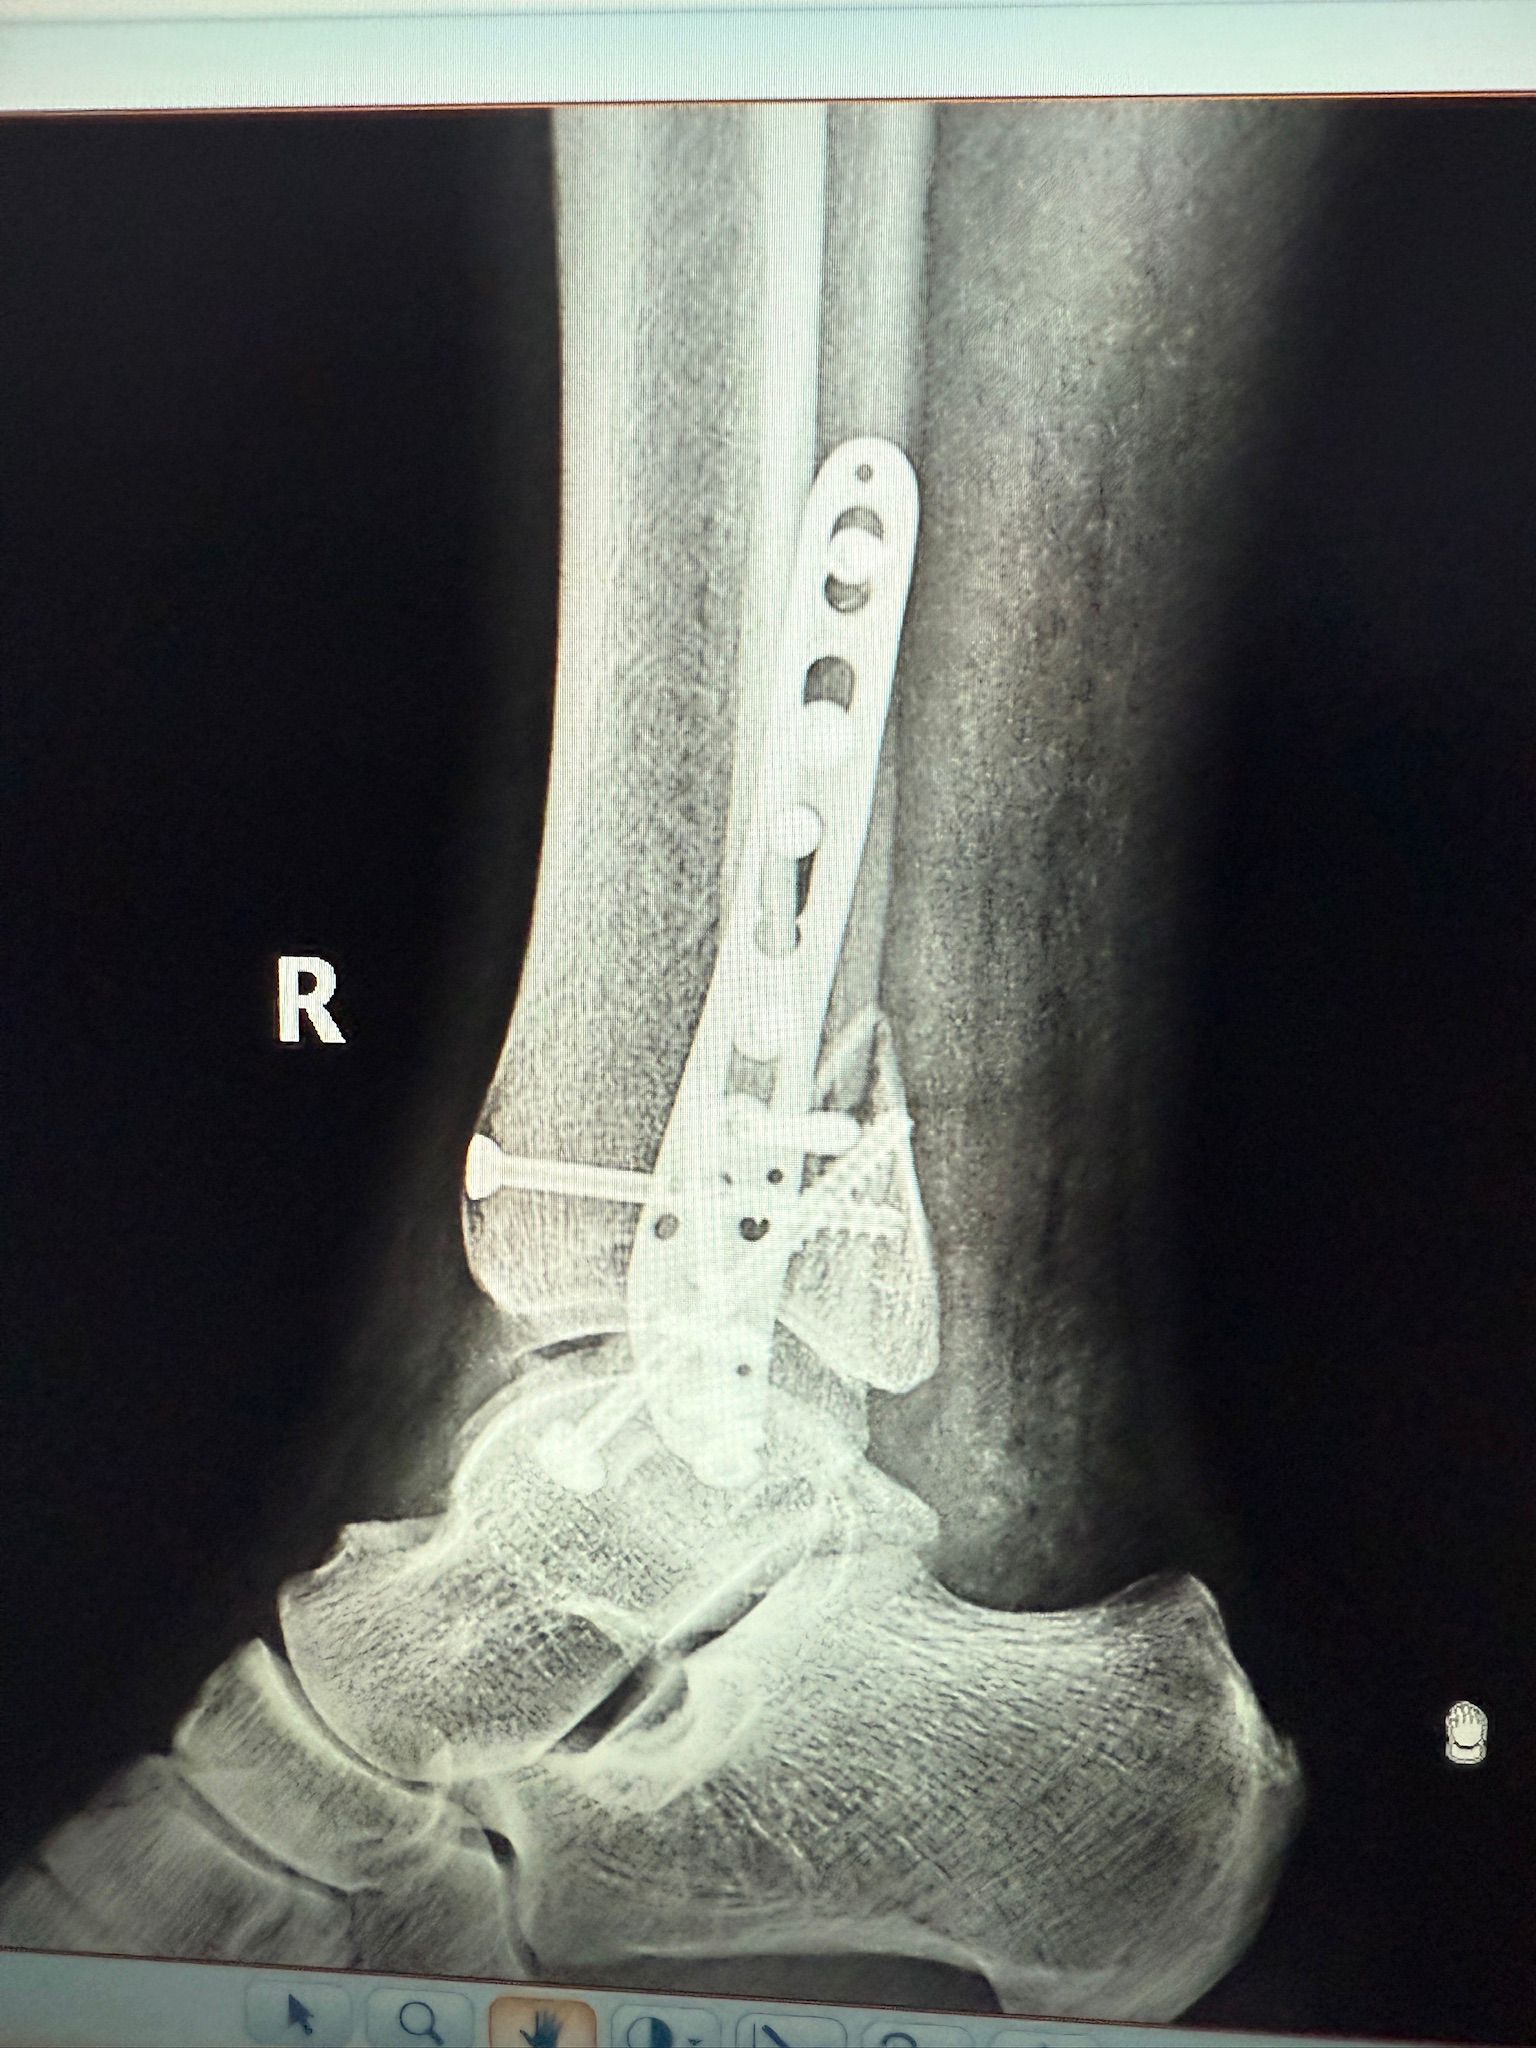

Imagini Clinice